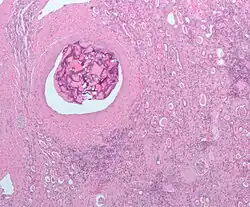

Enfin, on signalera la classe des dispositifs d'occlusion mécanique : coils et ballons détachables. Les coils sont généralement fait de platine et induisent la formation d'un thrombus à leur contact en raison de leur revêtement en polytéréphtalate d'éthylène.